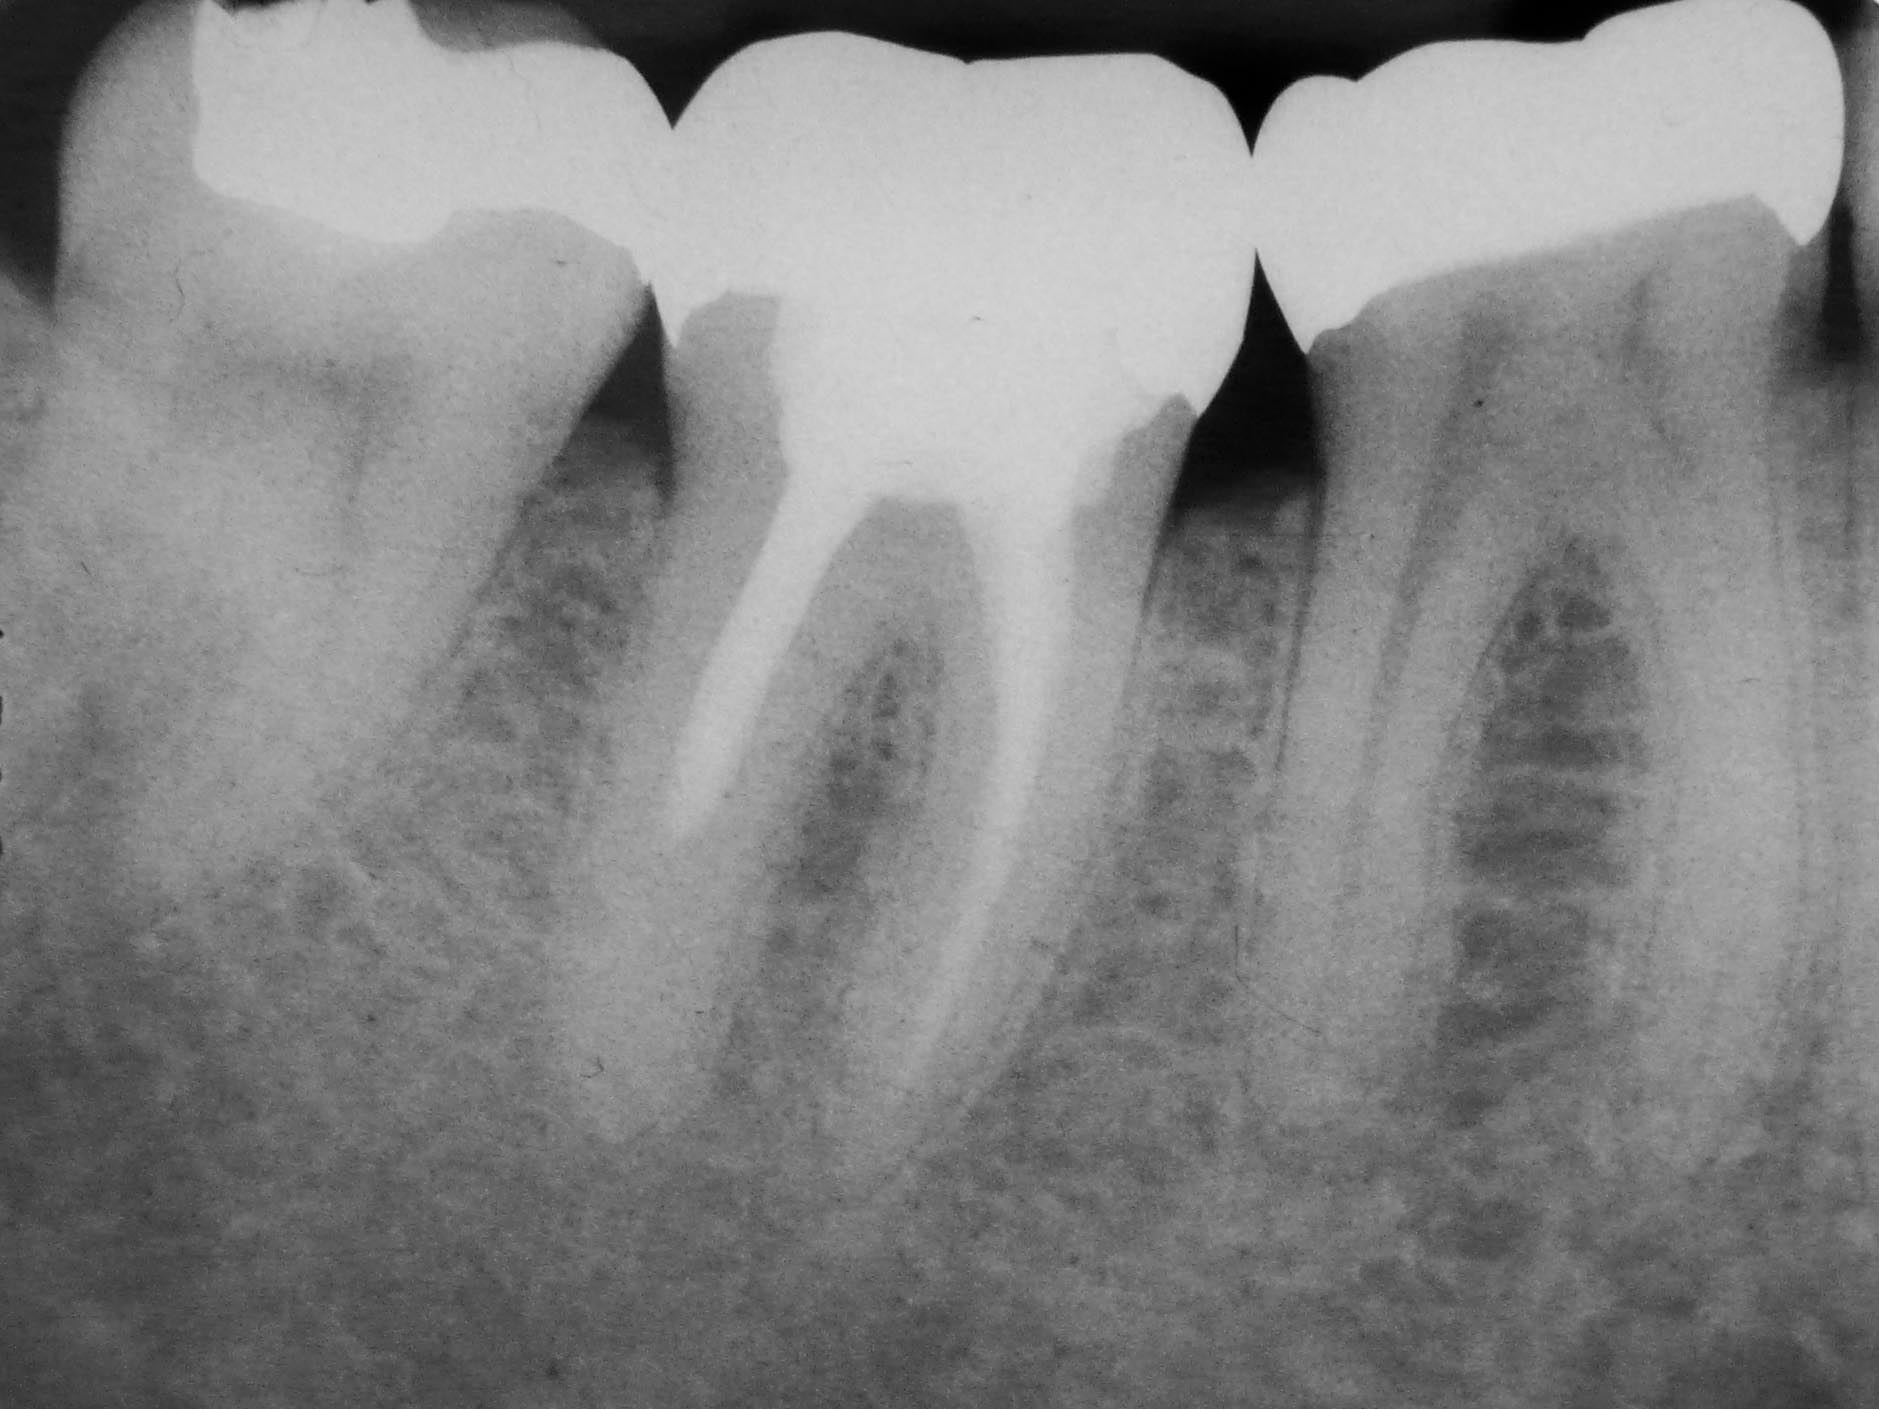

Rätselbild Veröffentlicht 31. August 2009 am 1879 × 1409 in Shit happens: Das Rätselbild – Die Auflösung